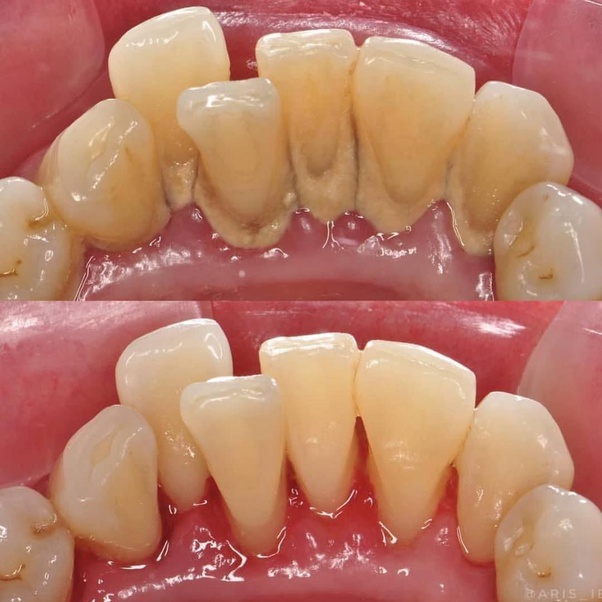

Scaling and polishing is a dental procedure designed to remove plaque, tartar, and surface stains from teeth. It's an essential part of maintaining oral hygiene and preventing gum diseases. For Kavita, it addressed her major concern – the stains that had dimmed her radiant smile.

After her first appointment, Kavita was amazed at the immediate results. Her teeth felt cleaner, and the stains that had plagued her for so long were significantly reduced. The procedure was painless, quick, and left her feeling rejuvenated. More importantly, it restored her confidence. She could now flash her smile without hesitation during client meetings and social gatherings.